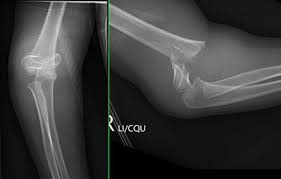

تعد جراحة العظام من أسرع المجالات الطبية تطوراً، ومع زيادة تعقيد الحالات وتوقعات المرضى، يصبح “تحسين الممارسة الجراحية” (Optimizing Surgical Practice) ضرورة وليس رفاهية.

من أهم ملامح تحسين الممارسة الجراحية هو معرفة “متى لا نتدخل جراحياً”. دراسة POSTFIX الأخيرة حول كسور الكاحل الخلفية قدمت درساً هاماً: